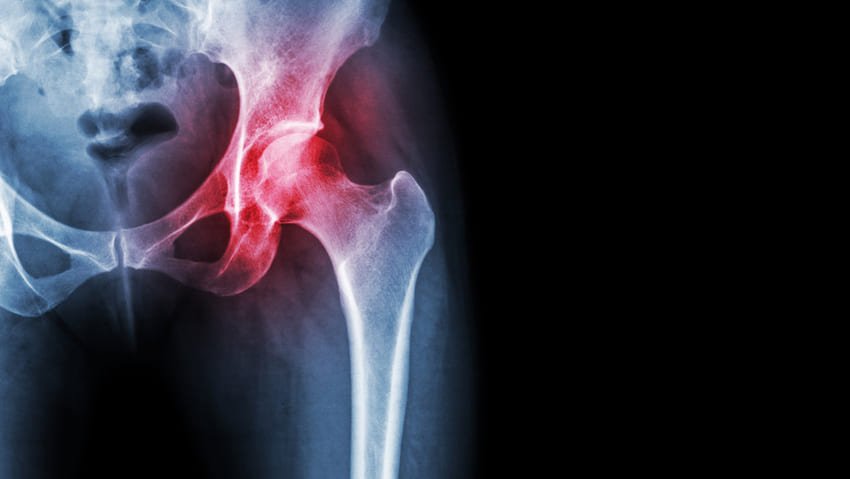

Kalça protezi ile genellikle hangi durumlar tedavi edilir?

Total kalça protezi genellikle aşağıdakileri tedavi etmek için kullanılır

- Osteoartritin neden olduğu eklem yetmezliği.

- Romatoid artrit

- Travmatik artrit

- Kalça kırıkları

- Avasküler nekroz

- İyi huylu ve kötü huylu kemik tümörleri ve diğer daha az yaygın durumlar